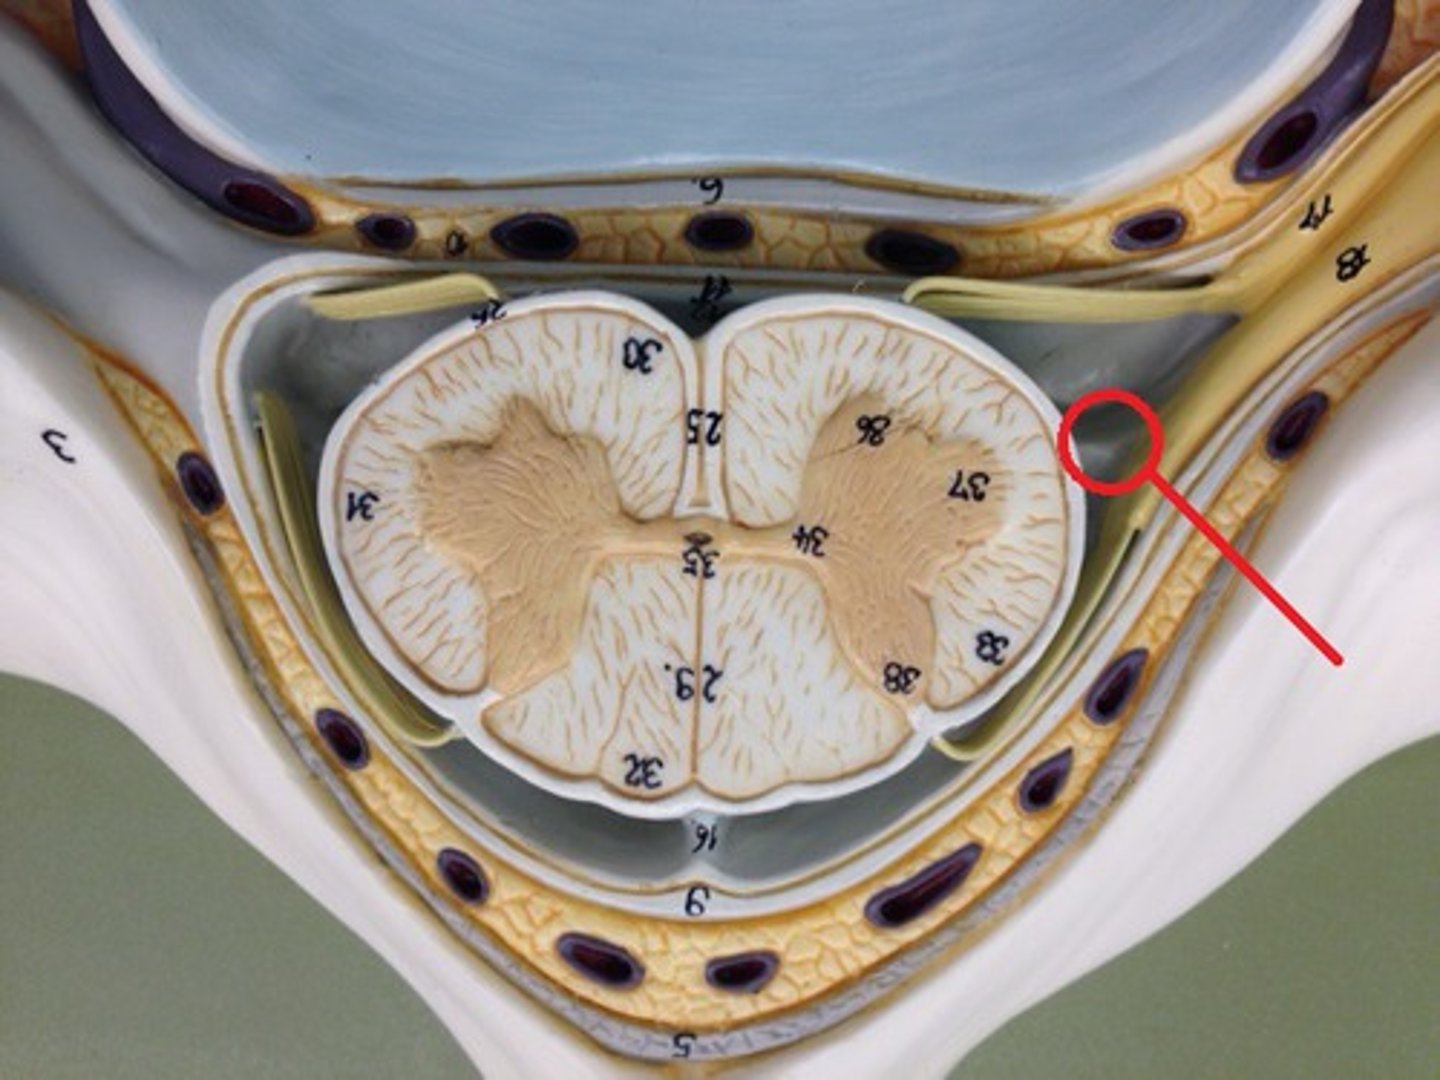

posterior median sulcus

anterior median fissure

posterior white column

anterior white column

lateral white column

posterior gray horn

anterior gray horn

lateral gray horn

gray commissure

Part of grey matter connecting the two halves of the grey matter in spinal cord

central canal

Hole in the center

Name this passageway

epidural space

dura mater

thick, outermost layer of the meninges surrounding and protecting the brain and spinal cord

subdural space

space between dura mater and arachnoid mater

arachnoid mater

middle layer of the meninges

B on model

subarachnoid space

a space in the meninges beneath the arachnoid membrane and above the pia mater that contains the cerebrospinal fluid

pia mater

the delicate innermost membrane enveloping the brain and spinal cord.

denticulate ligaments

extensions of pia mater that secure cord to dura mater laterally